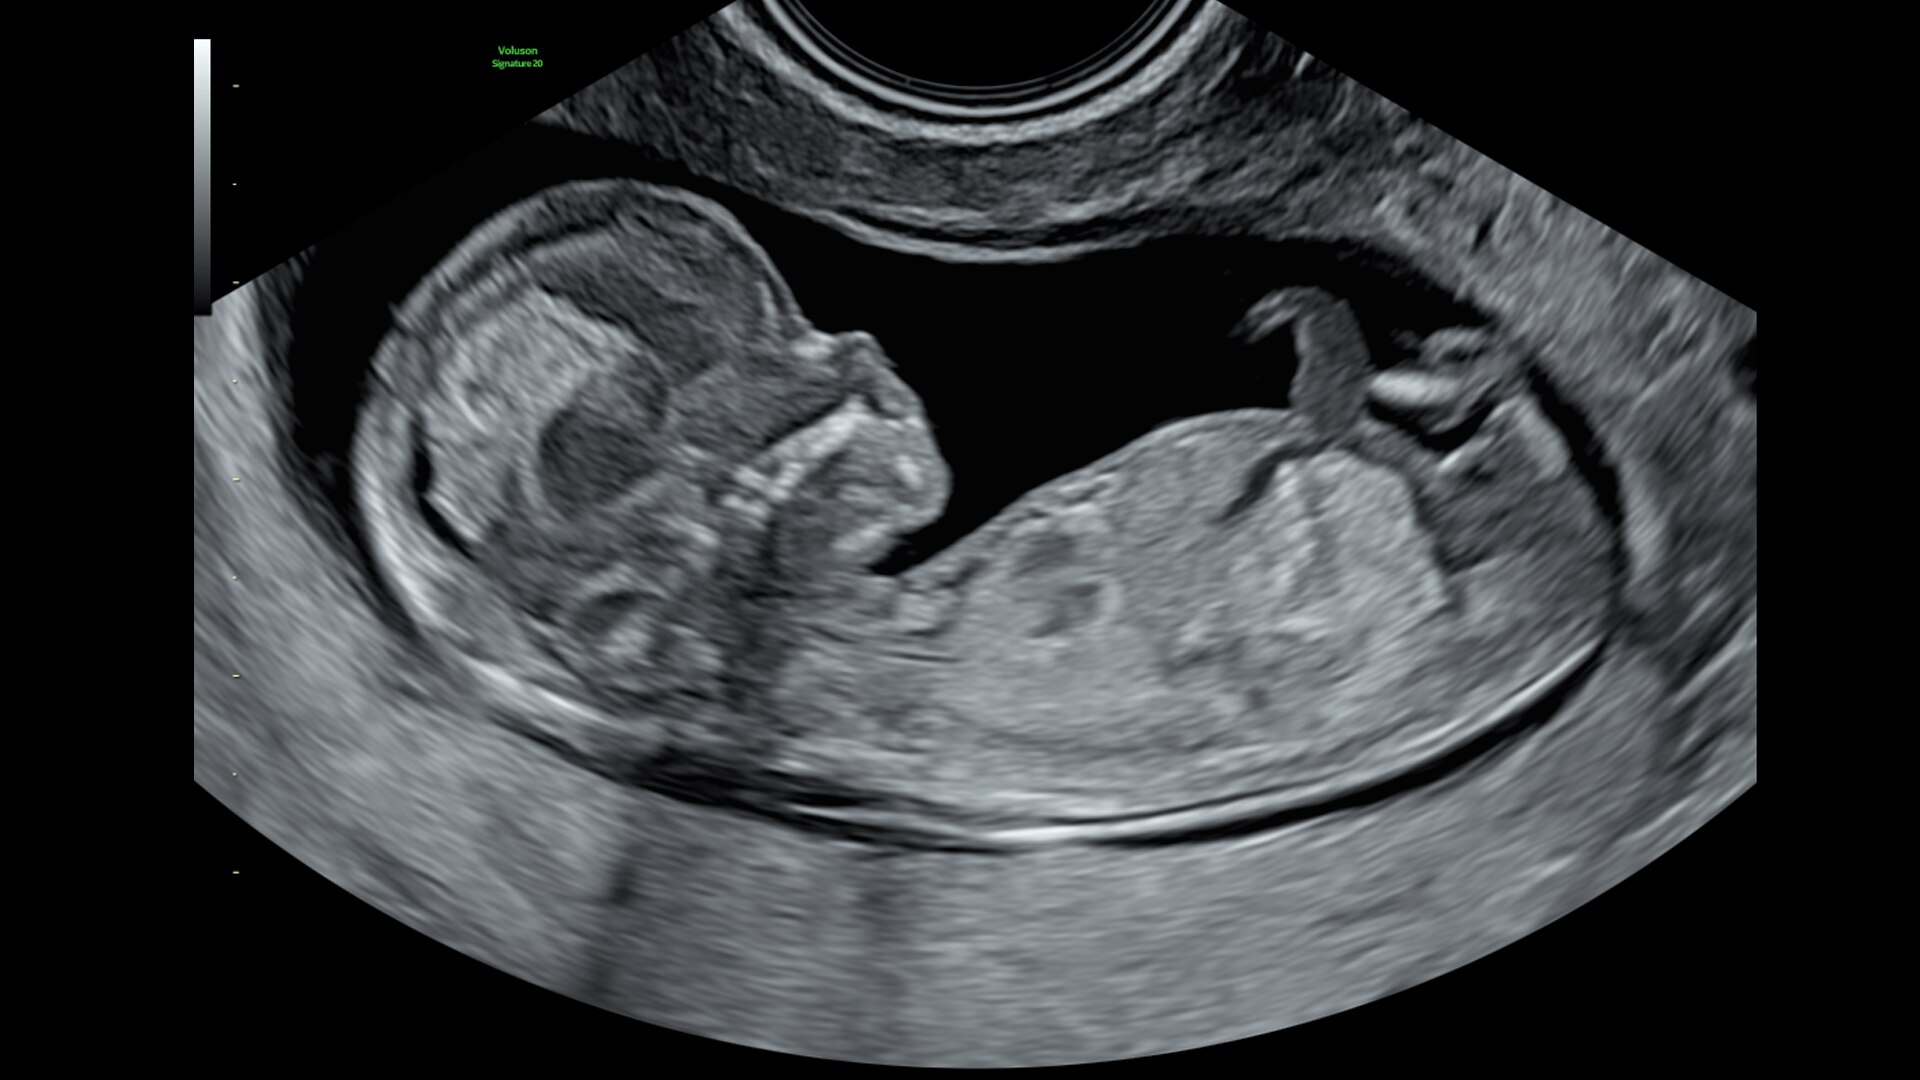

The Voluson Signature 20 is a top performer. Powered by a progressive, highly flexible system architecture and coupled with Voluson’s advanced transducer technology migrated from our premium Expert series platform, take a big leap in image quality. With a new level of depth and clarity, accelerate your diagnostic capabilities so you can always deliver your most confident care.

Advanced beamforming capabilities work in harmony with expert-level probes to deliver faster processing speeds and frame rates for enhanced detail and contrast resolution, greater color quality and sensitivity, and exceptional 3D/4D.